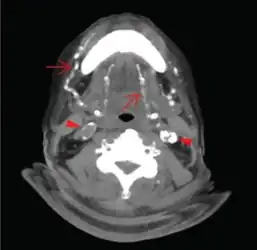

Often Mönckeberg's arteriosclerosis is discovered as an incidental finding in an X-ray radiograph, on mammograms, in autopsy, or in association with investigation of some other disease, such as diabetes mellitus or chronic kidney disease. Typically calcification is observed in the arteries of the upper and lower limb although it has been seen in numerous other medium size arteries.[5] In the radial or ulnar arteries it can cause "pipestem" arteries, which present as a bounding pulse at the end of the calcific zone. It may also result in "pulselessness." Epidemiological studies have used the ratio of ankle to brachial blood pressure (ankle brachial pressure index, ABPI or ABI) as an indicator of arterial calcification with ABPI >1.3 to >1.5 being used as a diagnostic criterion depending on the study.[14][15]

Axial CT slice at the level of C2-C3 soft tissue window setting setting. Extensive calcifications of the bilateral lingual and facial arteries are noted (arrows) as well as calcific plaques at bilateral carotid tree area (arrow heads). -